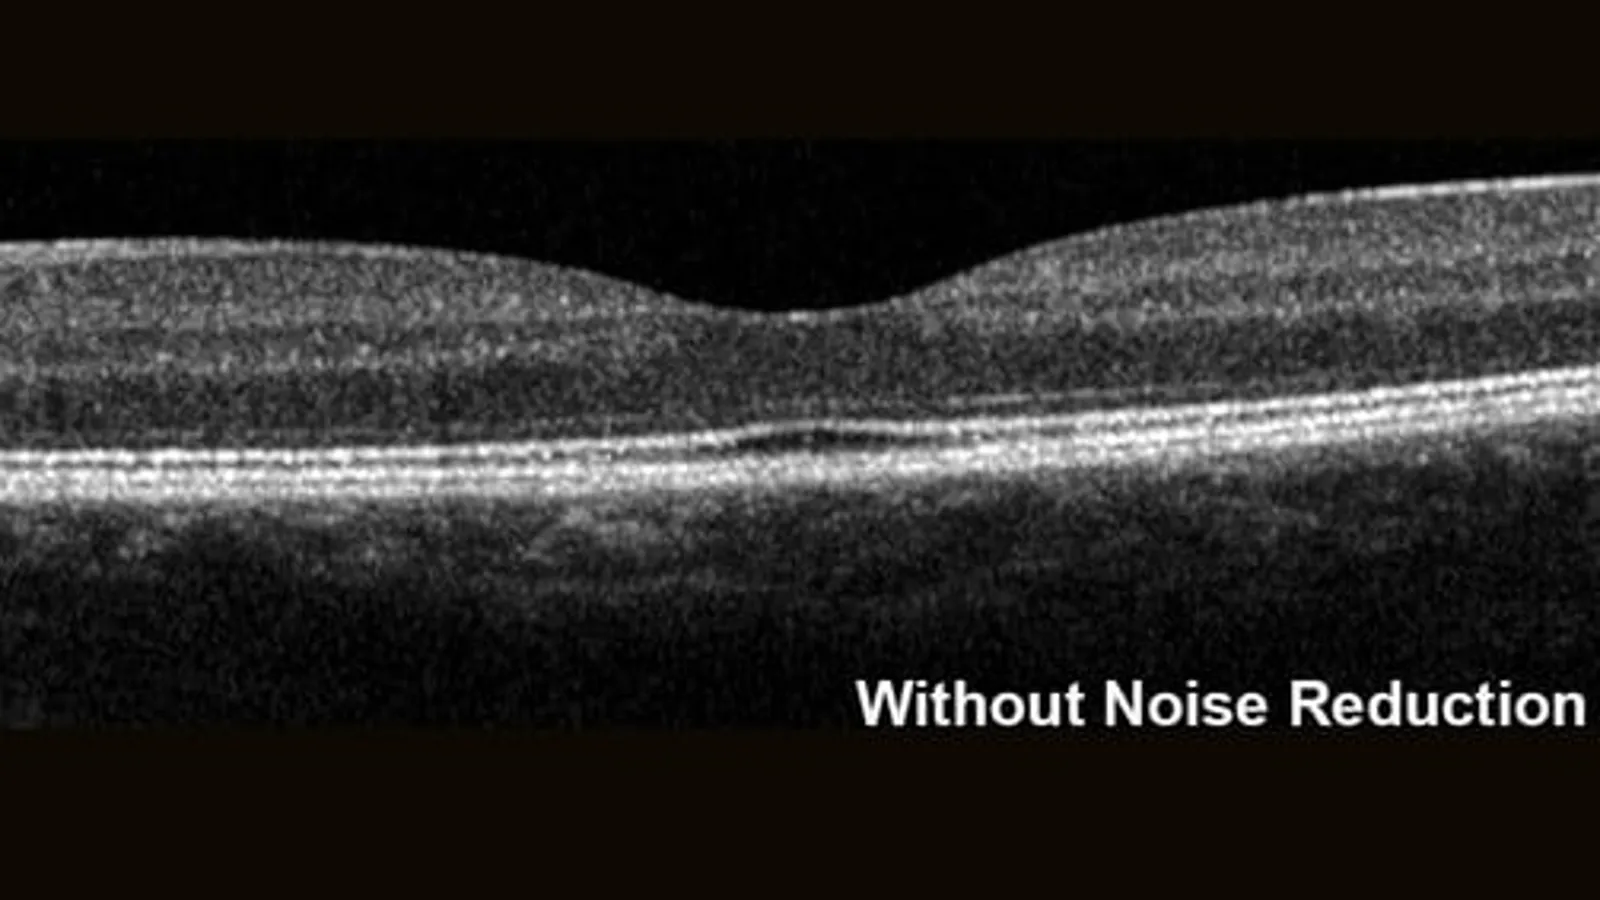

Riduzione del Rumore (Noise Reduction)

La tecnologia proprietaria Noise Reduction acquisisce più immagini nella medesima posizione anatomica, eliminando il rumore intrinseco dell’imaging OCT e della scansione laser. Mediando in tempo reale fino a 100 B-scan, distingue le informazioni strutturali dal rumore e fornisce immagini ad alto contrasto con dettagli eccezionali, anche nelle scansioni volumetriche.